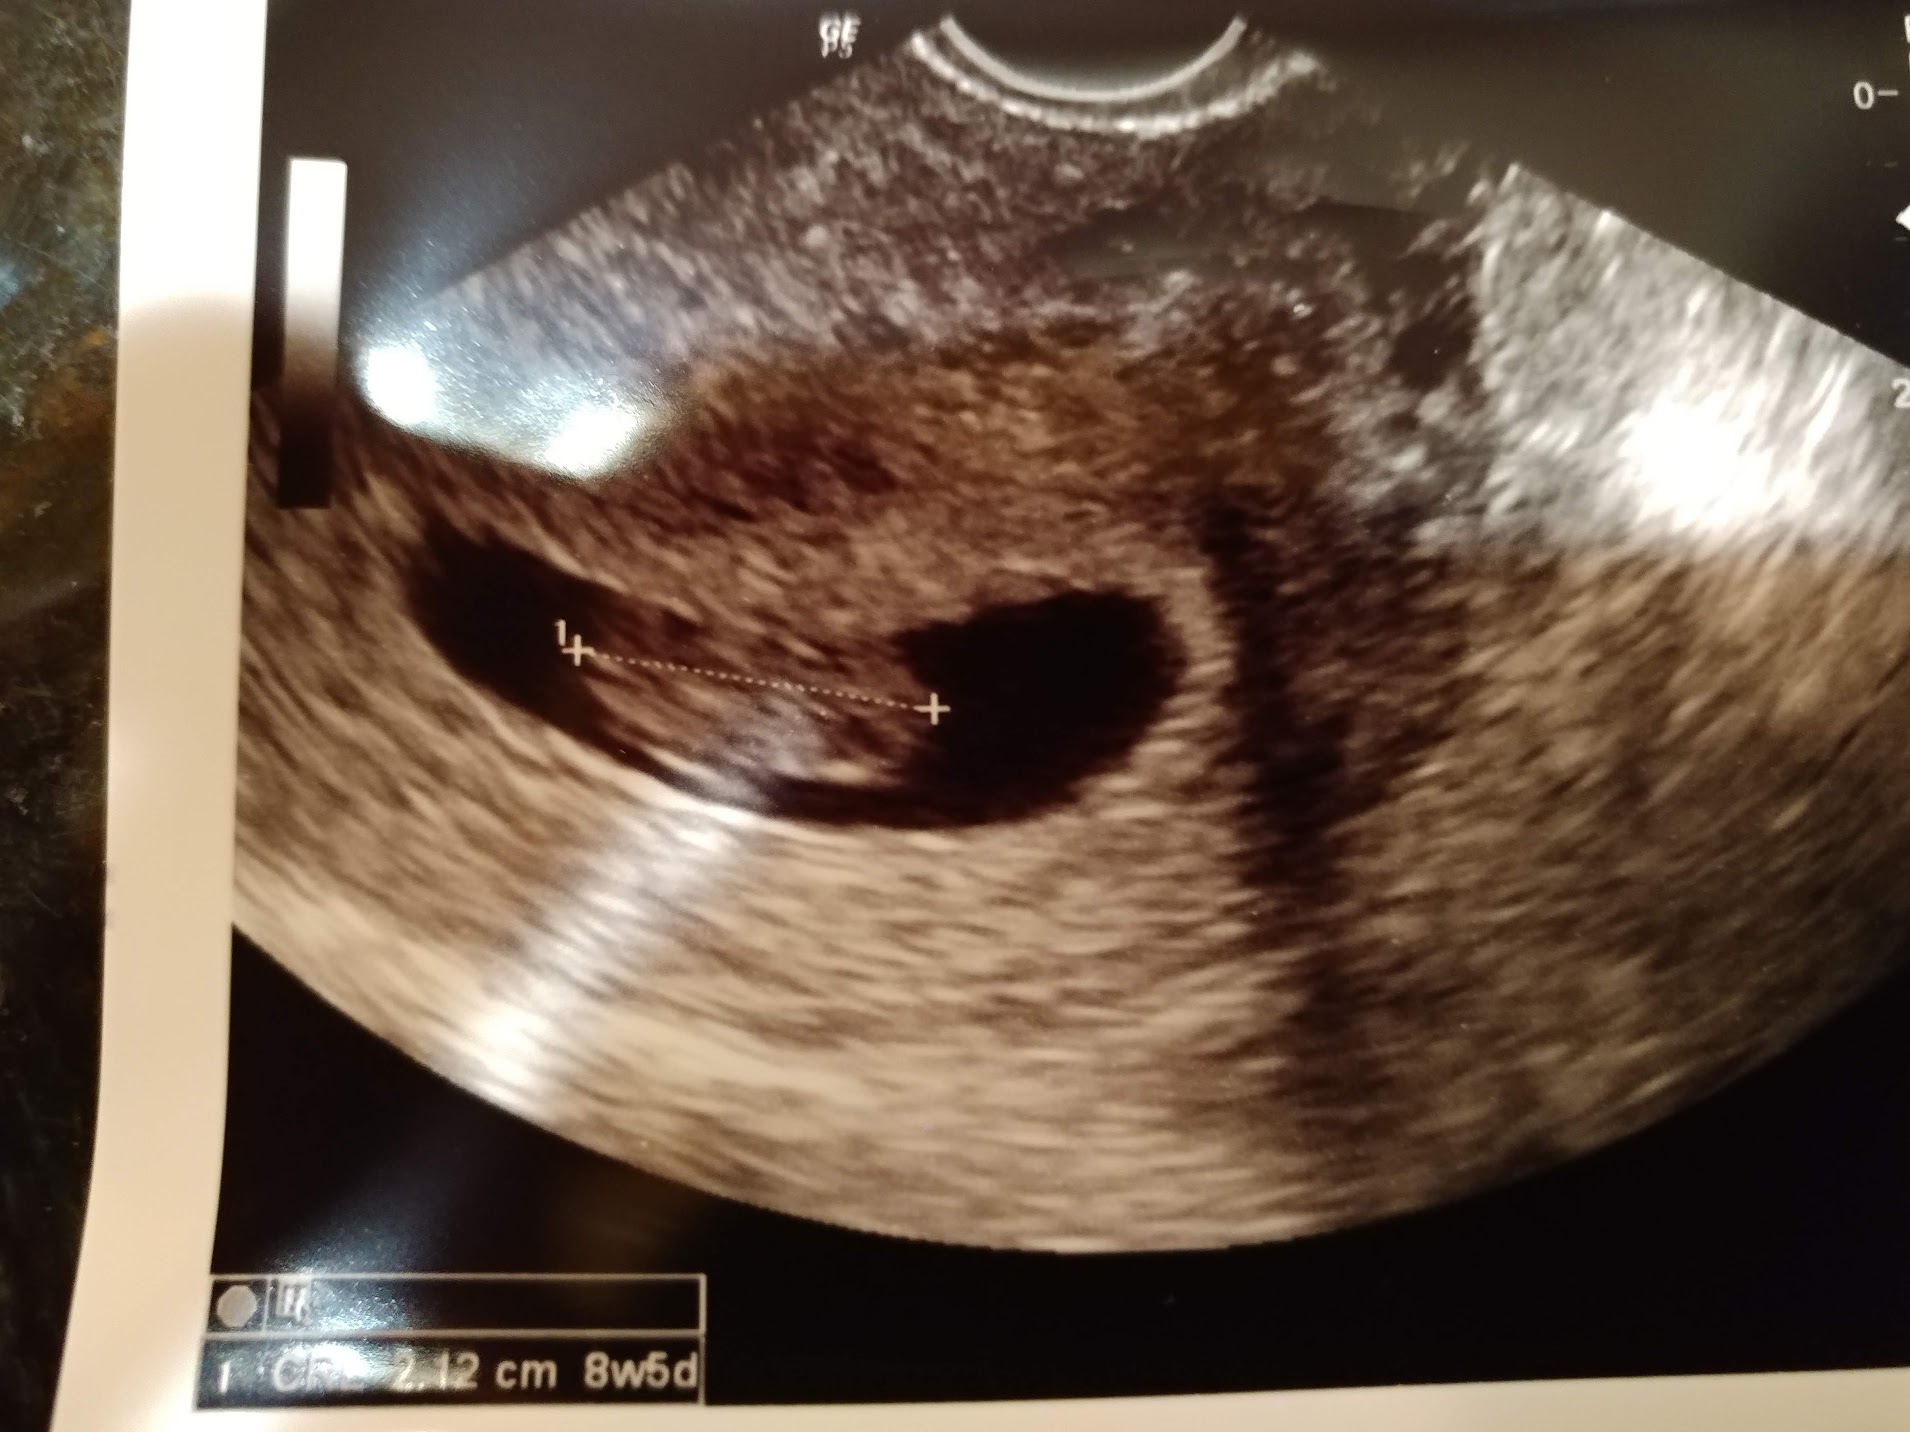

I also posted in the private but it looks like less traffic there. I would REALLY appreciate guesses. We did a VERY strict sway for 3 months, and I find out Friday morning. Ramzi is 8w3d transvaginal and nub is 12w3d abdominal. Thank you so much for guessing!!!!! I'll be sure to update.Attachment 41231Attachment 41232